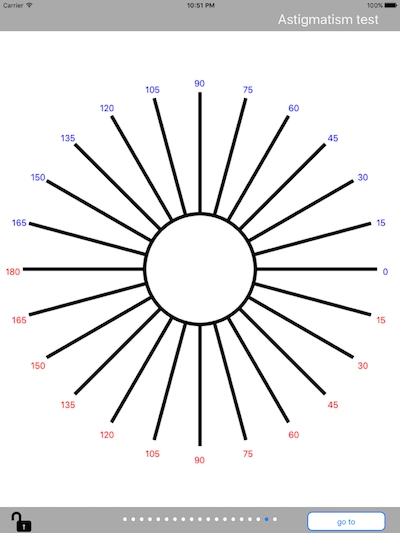

散光圖片

散光度數測試圖 (48)

散光度數測試圖 (49)

散光度數測試圖 (5)

散光度數測試圖 (50)

散光度數測試圖 (51)

散光度數測試圖 (6)

散光度數測試圖 (7)

散光度數測試圖 (8)

散光度數測試圖 (9)

散光度數測試圖 (39)

散光度數測試圖 (4)

散光度數測試圖 (40)

散光度數測試圖 (41)

散光度數測試圖 (42)

散光度數測試圖 (44)

散光度數測試圖 (45)

散光度數測試圖 (46)

散光度數測試圖 (47)

散光度數測試圖 (35)

A:判斷自己有沒有散光,最簡單的方法是使用散光表來測試。散光表是一種簡單、方便的方法,但是它的準確度不是特別精確。在配鏡的情況下一般再用裂隙法,或者是交叉圓柱鏡法來精調散光的度數。散光表在網上可以看到,它類似於鐘錶的盤面,有12個數字。各個鏡線……